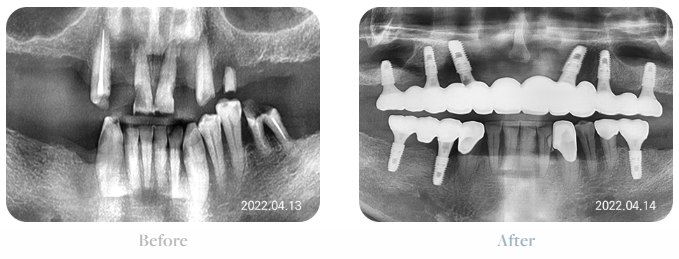

전체임플란트후기 심미성

전체임플란트는

사진에서 확인할 수 있듯이

심미성을 회복시킵니다.

치아가 얼마 안 남았다면

점점 입매는 입의 안쪽으로 말려 들어가게 됩니다.

빈 공간을 채우려는 우리 몸의 자연스러운 반응이죠.

이는 노쇠함을 돋보이게 하기 때문에

노화에 대한 아쉬움이 증폭됩니다.

전체임플란트후기 심미성을 보면

식립 후 고정된 인공 치아를 통해

입매가 자연스러워진 것을 확인할 수 있습니다.

전체임플란트후기 기능성

기능성을 회복시킵니다.

잇몸과 치아의 심각한 손상은

음식을 씹을 때마다 고통을 주게 됩니다.

자연스럽게 부드러운 음식이나

자극적이지 않은 음식만 찾게 되는데요

손상이 악화되어 있다면

그마저도 섭취가 힘들게 됩니다.

전체임플란트후기 기능성을 보면

편안한 저작이 가능함을 확인할 수 있습니다.